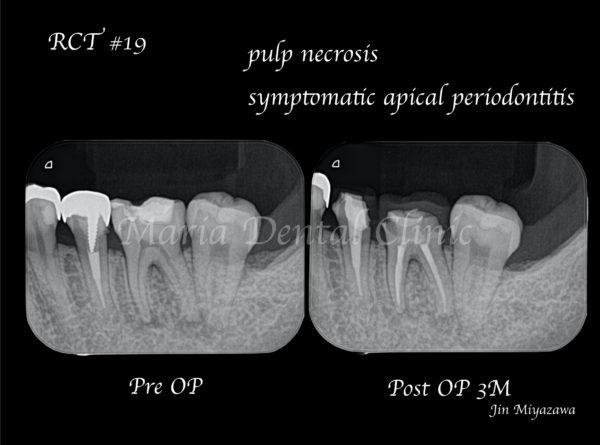

【症例】初回根管治療(歯髄壊死)|患者様利益を考えた精密根管治療

治療内容 抜髄(初回根管治療)|精密根管治療

昨日から「何もしなくてもズキズキ痛む」ことを訴えて来院された患者様です。来院当日は痛み止めを服用し少し痛みが落ち着いている状態ですが、数時間で痛み止めが効かなくなってしまうとのことでした。

当院での診査の結果、歯髄壊死・根尖性歯周炎と診断しました。カウンセリング当日は痛みが非常に強かったため応急処置まで進め、残りの治療は精密根管治療で行うことになりました。

応急処置を施した結果、応急処置後に痛みから開放されたとのことで、当日予定通り精密根管治療を開始しました。

治療回数は2回、1回目は根の中を徹底的に綺麗にし、2回目の治療で根管を封鎖、土台(支台築造処置)、仮歯の作製まで終了しました。

治療終了後、良好に根の中にバイオセラミックが充填され封鎖できていることを確認し(画像A)、3ヶ月後の経過観察にて、痛みや違和感がないことはもちろんのこと、術前、術後に確認できていた根尖性歯周炎の透過像の縮小を確認(画像B)し経過が良好であると判断しました。

経過観察当日に被せ物(最終補綴処置)の型取りを行い、次回セットし終了しました。次回は1年後に経過観察を行う予定です。